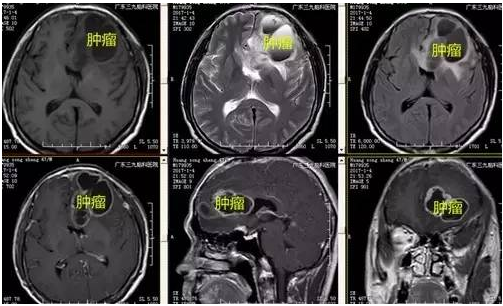

黄某某,男,47岁,头痛1周入院,入院后予完善相关检查,术前磁共振显示额叶病变最大直径5公分,肿瘤囊性变,左侧额叶多发囊状异常信号影,右侧半卵圆中心异常信号影。完善术前准备后,手术由神经外一科主任张良主刀完成,行全麻下左侧额叶胶质瘤+鞍区脑膜瘤切除术,术程顺利,术后复查头颅CT及MR提示术后改变,肿瘤全切除,术后病理提示间变性少突胶质细胞瘤(WHO III级),鞍区病变提示过渡型脑膜瘤(WHO I级)。

↑术前检查

单纯少突胶质细胞瘤往往很局限,以膨胀性生长为主,生长缓慢。瘤内常有不同程度钙化,钙化常发生在肿瘤血管壁内,亦可发生于瘤内任何部分及瘤外脑组织,间变性少突角质细胞瘤常无或轻度瘤周水肿,占位效应轻,增强扫描强化常不显著,增强多为均匀性,少数为环形增强,恶性者增强明显,有中等以上瘤周水肿,钙化少或不明显。本例有明确囊性变,增强不明显,有环形强化,轻度瘤周水肿,占位效应轻。